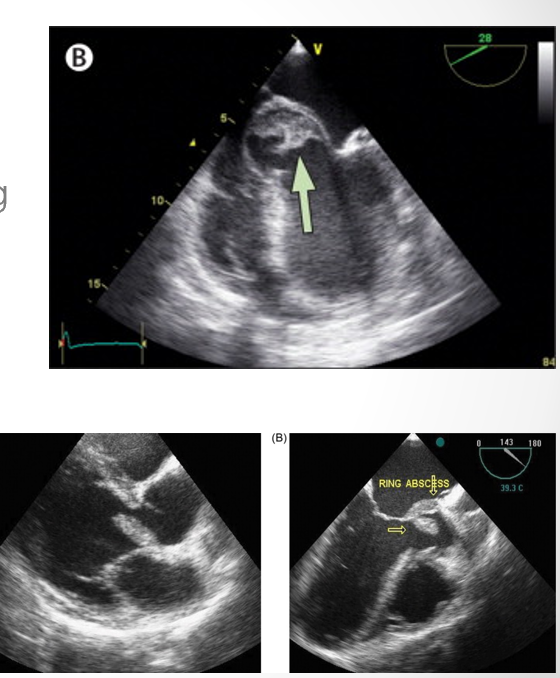

what is seen here?

endocarditis vegetation of tricuspid leaflets and infectious abscess of aortic annulus

periannular absces adjacent to sewing ring